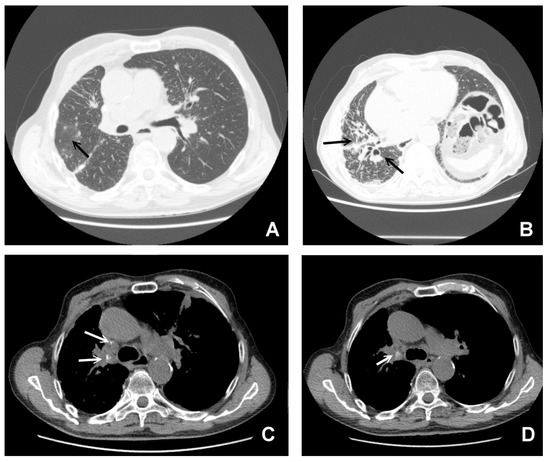

3. CT in Pulmonary Sarcoidosis, Imaging Findings and Classification

The Integration of 18-Fluoro-Deoxyglucose (FDG) Positron Emission Computed Tomography (PET/CT)